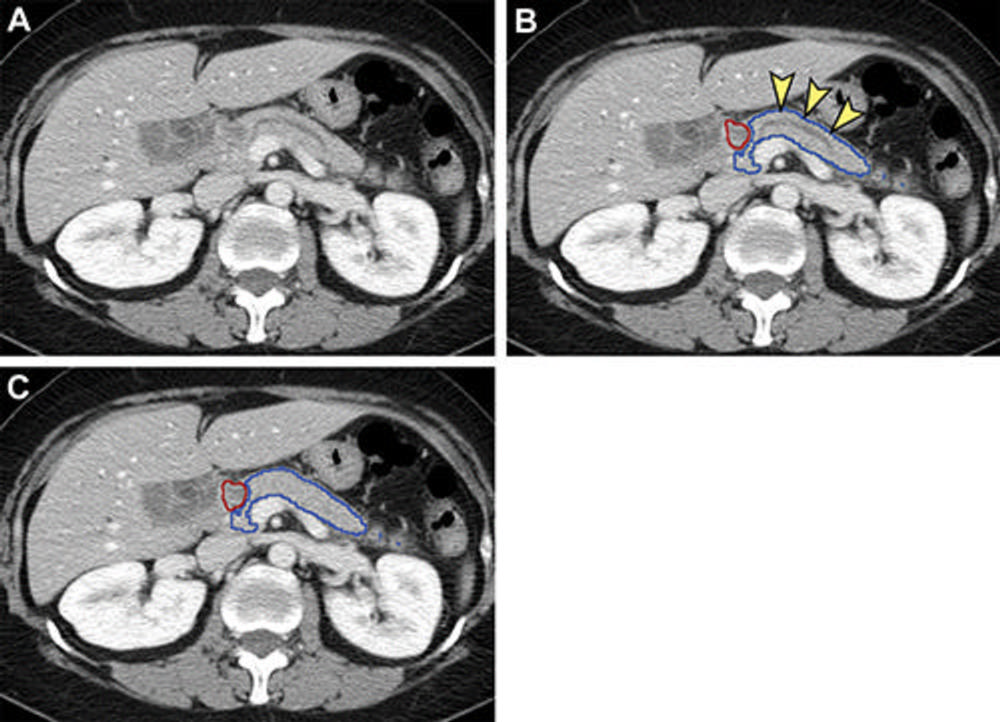

Figure 4. False-negative (A, B) and false-positive (C, D) tumor segmentation by the segmentation model. Blue and yellow outlines indicate normal pancreas and tumor segmented with the segmentation model, respectively. Images in the left column are original unannotated CT scans. (A, B) Tumors (red outline) were not segmented by the segmentation convolutional neural network. The upstream pancreas shows secondary signs of pancreatic cancer, including dilation of the pancreatic duct with abrupt cutoff (arrowhead in A) and parenchymal atrophy with dilation of the pancreatic duct (arrowhead in B). (C) Collateral veins secondary to idiopathic portal vein thrombosis were incorrectly segmented as tumor by the segmentation model. (D) Pancreatic parenchyma adjacent to biliary stents (arrowhead) placed for relieving obstructive jaundice from hepatocellular carcinoma was incorrectly segmented as tumor by the segmentation model.

High-res (TIF) version

Figure 5. Analysis of nontumorous portion of pancreas with or without secondary signs of pancreatic cancer by classification models. Blue outline represents the portion of the pancreas analyzed with classification models. The tumor (red outline) was not identified by the segmentation model; thus, it was not analyzed by classification models. (A) Unannotated CT image in a patient with pancreatic head cancer. (B) Nontumorous portion of the pancreas shows secondary signs of pancreatic cancer (dilation of pancreatic duct with abrupt cutoff [arrowheads]) and was classified as cancerous by the classification models. (C) Nontumorous portion of the pancreas appeared normal and was classified as noncancerous after the dilated duct was replaced and imputed with surrounding normal-appearing pancreas parenchyma.